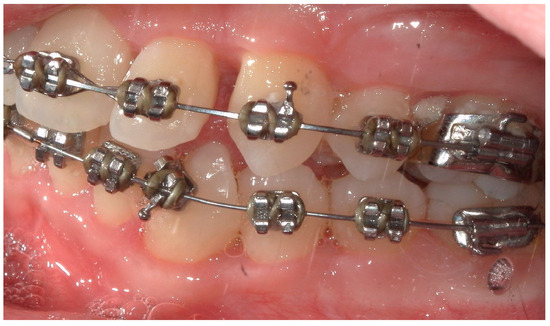

4.1. Case 1

4.2. Case 2